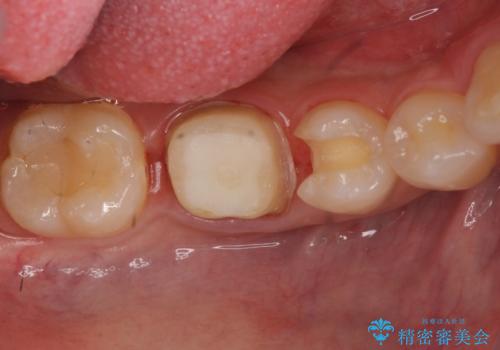

- 他の歯を治療中にレントゲン写真を撮ったところ虫歯を発見。

どうせなら1つ奥の銀歯も白くしたいとのご希望があり、2本ともセラミックにて治療をしていくことになりました。

虫歯治療に加え、奥の銀歯も同時にやり替えました。